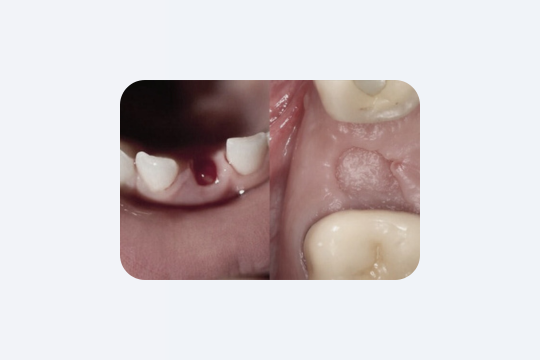

«Серый налёт» в лунке

Примерно на 3–4 день заживления вы можете заметить серый налёт в лунке. Не пугайтесь — у вашего организма всё идёт по плану. Это фибриновая плёнка — совершенно нормальный и естественный этап заживления. Она образуется из фибриногена вашей крови в ответ на повреждение тканей. Не нужно её сдирать или пытаться удалить самостоятельно. Со временем она рассосётся, и на её месте сформируются здоровые дёсны.

«Бугорок» на дёснах после удаления

Это костная мозоль. Обычно она не вызывает никаких проблем. Её образование связано с травмированием костной ткани во время удаления зуба. Костная мозоль едва заметна, может выглядеть как твёрдая, шероховатая или гладкая шишка на дёснах. Она безболезненна, но может вызывать дискомфорт из-за того, что вы её ощущаете.

В большинстве случаев лечение не требуется, однако в некоторых ситуациях, например при протезировании, врач может порекомендовать её удалить.